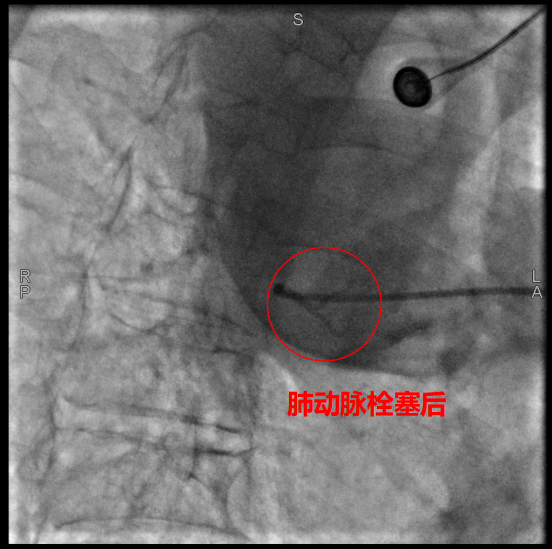

术中,数字减影血管造影(DSA)显示患者右侧支气管动脉及胸廓内动脉增粗紊乱,末梢血管可见造影剂点状外溢,明确为主要出血责任血管。团队采用400 µm栓塞微球及560–710 µm明胶海绵颗粒,对出血动脉远端实施精准栓塞,实现“末梢血管封堵”;同时,对肺动脉分支血栓相关区域也予以栓塞处理,以全面控制咯血来源。术后造影确认出血完全停止,患者安返病房后未再咯血,胸闷、气促等症状显著缓解。